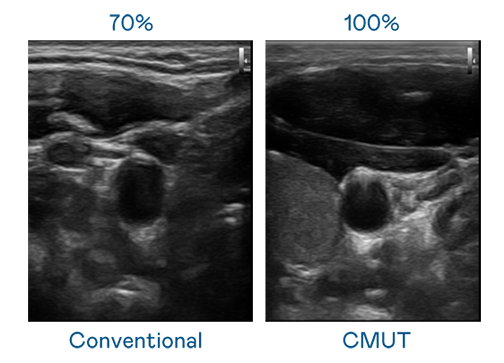

LEYU官網(wǎng)運用 TFT 陣列 (Array) 制程延伸尖端感測技術,開發(fā)出多種感測元件的LEYU官網(wǎng)。高解析度、品質穩(wěn)定且可量產的 CMUT 元件,可制作高解析度超音波探頭、貼片型探頭,對病患實施精準檢測與長時間生理監(jiān)測。